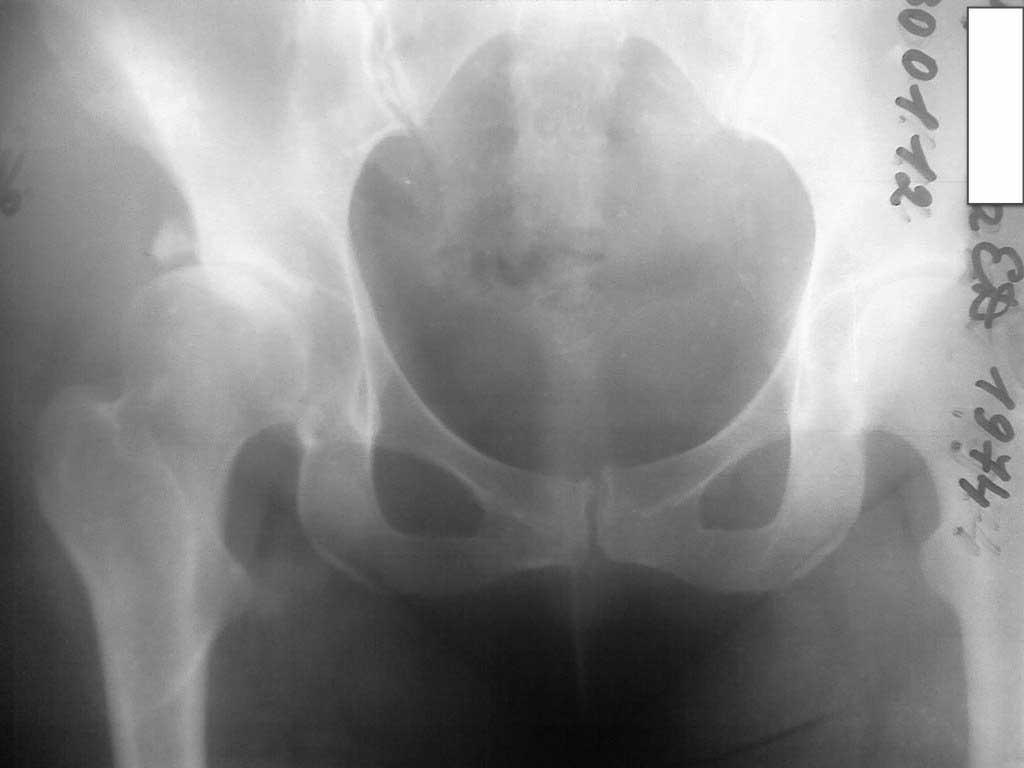

Добавляю снимков для "информационной поддержки принятия решения" (ну, нравится мне это выражение )). Поступило предложение выполнить артроскопию для оценки сохранности хряща. Насколько это необходимо?

Спасибо.

Здесь явная дисплазия с стрессовым переломом латерального края вертлужной впадины. Генез стрессовых переломов за счет нагрузки головкой в латеральный край, где сперва образуется зона разрежения, затем образование кисты в толще кости. Продолжающиеся нагрузки приводят

к стрессу, и истонченные стенки не выдерживают, что приводит к перелому.

При рентген картине СЕ (Center Edge) меньше 5 градусов и вальгус около 142 градусов, а также молодой возраст является прямым показанием для Периацетабулярной Остеотомии и Варусной остеотомии.

Для расчета остеотомии необходимы качественные снимки прямого таза и боковой снимок. Установка бокового снимка описана в прежних дискуссиях. Прямой снимок дает ответы о состоянии хряща, а артроскопия для ПАО является малоинформативным исследованием. А имеющиеся

небольшие повреждения хряща восстановится при изменении остетотомией геометрии нагрузки.

Для полного решения проблемы в ближайщее время необходимо произвести периацетабулярную и варусную остеотомию одновременно. После изменения геометрии без нагрузки краевой перелом срастется даже без фиксации.

При отсутствии возможности оперировать в данное время можно попробовать только варусную остеотомию, которая решит проблему частично.